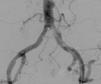

A pesar de que la ecografía Doppler, repetida en 2 ocasiones, no sugiere estenosis de arteria renal, se decide arteriografía en la que se objetiva obliteración de la porción distal de la ilíaca común izquierda (fig. 1), permeabilidad del resto del eje ilíaco y de la arteria del injerto renal. Se predilata y se coloca un stent a nivel de la obliteración, con recuperación casi completa del calibre vascular (fig. 2).

Inmediatamente después presenta poliuria de 6l en 24h, y excelente control de la PA. Además, a las 24h, mejoría de la función renal con creatinina 2,5mg/dl, sin necesidad de nuevas sesiones de ultrafiltración. En el control efectuado al mes, normotensa con 3 fármacos (α-bloqueante, ß-bloqueante y diurético), y mejoría de la función renal hasta creatinina de 1,85mg/dl.